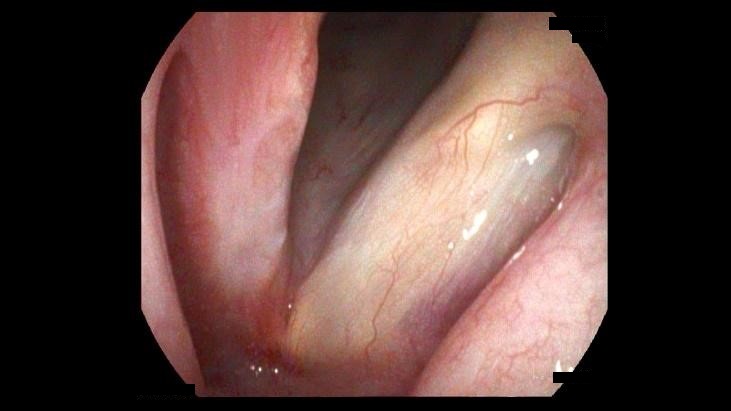

Vocal Fold Polyp

Vocal fold polyps are considered phonotraumatic lesions which are lesions that form from voice abuse, misuse or overuse. Often the inciting factor is hemorrhage from a micro vessel into the lamina propria that stretches the epithelium of the vocal fold forming the finger-like outpouching. The blood dissipates over time, but the outpouching may remain requiring surgical intervention and often voice therapy to correct the traumatic voice habits. This is a case of a middle school teacher who had persistent voice changes for several years